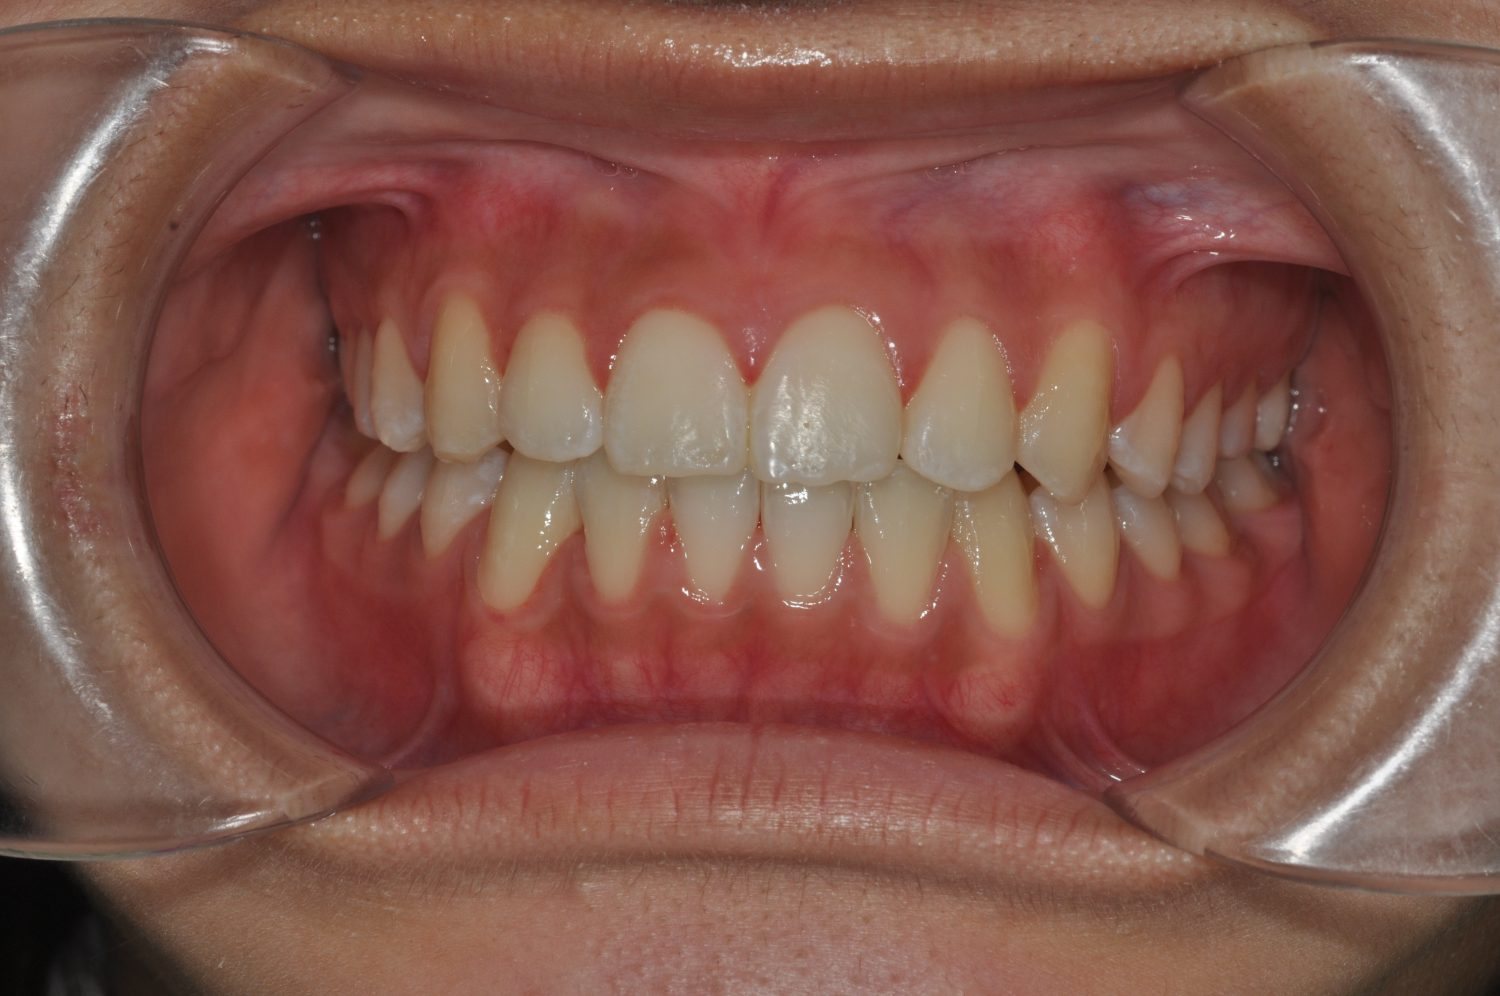

| 主訴 | 前歯の出っ歯を直したい |

| 治療内容 | 上下顎とも標準範囲であるが、上下顎前歯ともに唇側傾斜による、上下顎前突。上顎小臼歯を抜去し配列を行うこととした。 |

| 治療費 | Ⅱ期治療費:770,000円 (税込) 調整料 5,500円 (税込)×23回 保定時:22,000円 (税込) 計 918,500円 (税込) |

| 治療期間 | 2年1ヶ月 |

| 治療回数 | 25回 |

| 想定されたリスク | 矯正器具の装着に伴い、むし歯や歯周病のリスクがありました。また、歯根吸収や歯肉退縮のリスクもありました。 |

上下顎前歯の唇側傾斜による上下顎前突。オーバージェットが大きいため、上顎のみの抜歯で配列を行った。